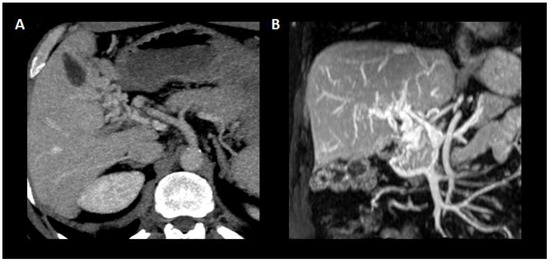

Figure 4.

Cavernous transformation of the portal vein. (A) Axial plane showing the substitution of the main portal vein trunk by porto-portal collaterals originated from the vasa vasorum of the portal vein. (B) Coronal plane of the portal vein and its cavernous transformation with the entanglement of the new vessels composing the porto-portal collaterals.